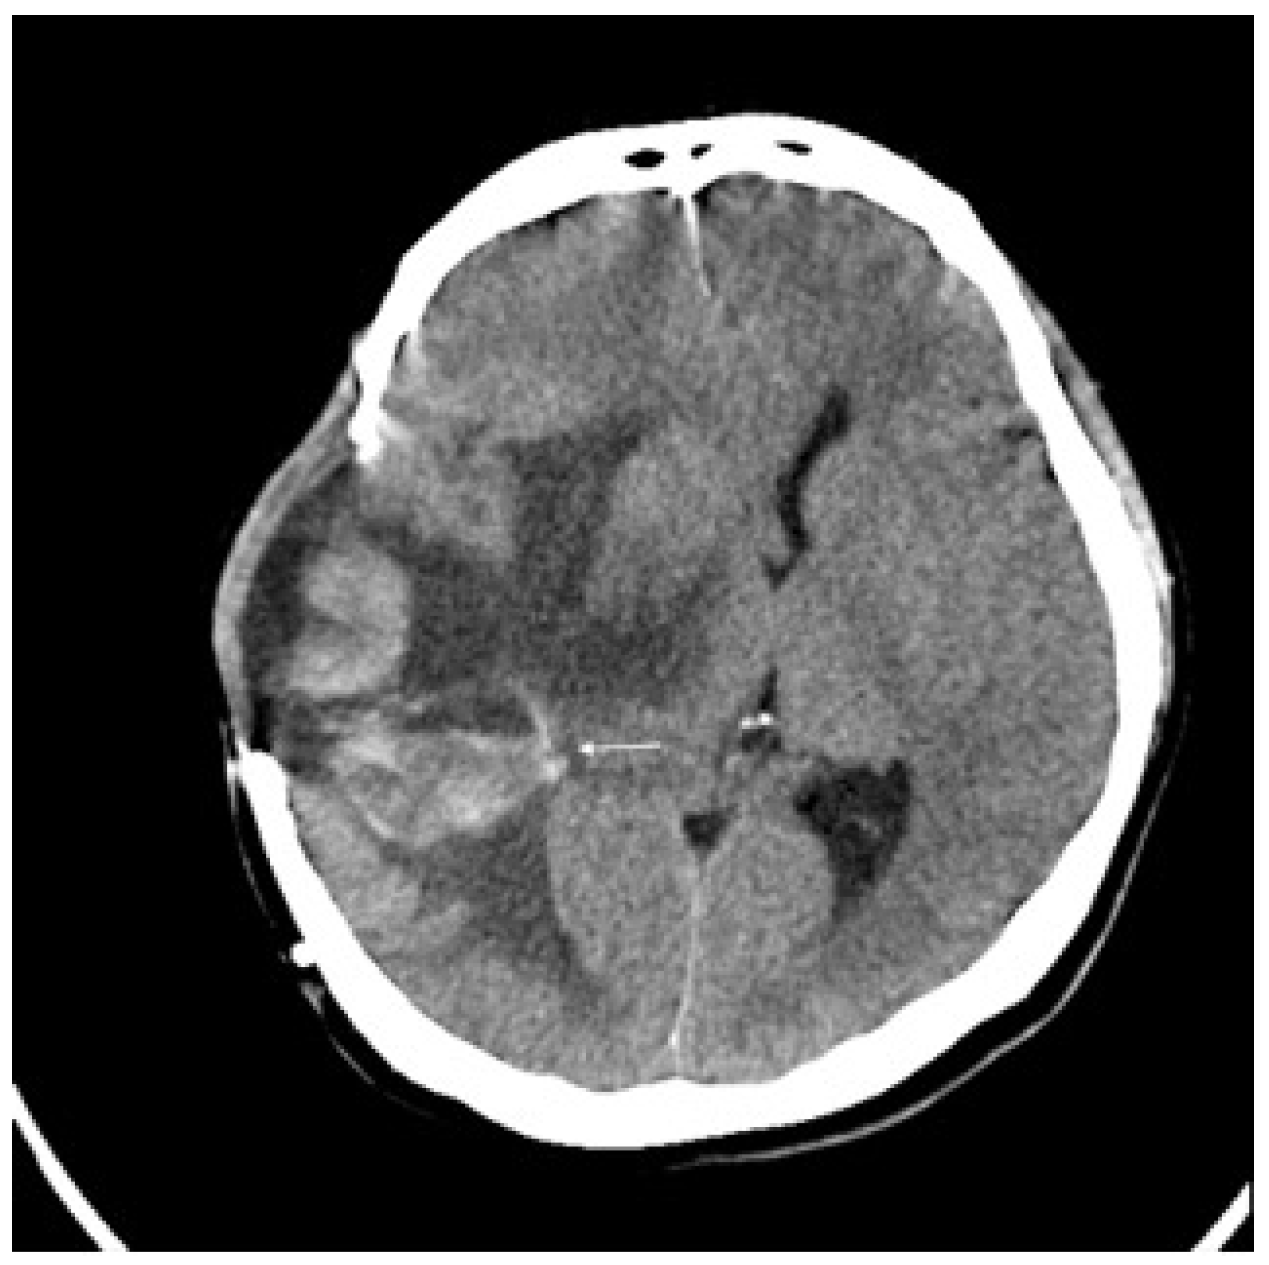

2. Detailed Case Description

| Present case | 43/ F/ Asian | Right temporal (intracranial) | Leptomeningeal (spine); bone, liver, etc. | Surgery (subtotal) + Gamma Knife; Early pembrolizumab; Ipilimumab on progression | Early (~1-month post-transformation) | Improved mobility after pembrolizumab; later decline | ~15 months after the initial diagnosis | ~15 months PT (2.5 years from initial) | 50% |